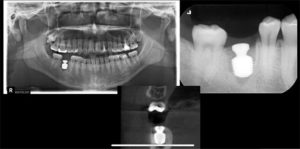

今回のケースはルートメンブレンテクニックを使った症例、抜歯即時埋入における症例の2症例でした。

今回は前歯部における歯根の一部を保存して、唇側の骨を温存するルートメンブレンを使ったインプラント埋入や臼歯部における抜歯即時埋入など難易度が高い症例ばかりでした。

インプラント治療においてどれだけ既存骨が吸収されずに埋入できるかが非常に重要になってくるため、このルートメンブレンテクニックや抜歯即時埋入が大切になってくるため、技術面だけでなく、知識面も深める必要があると感じました。